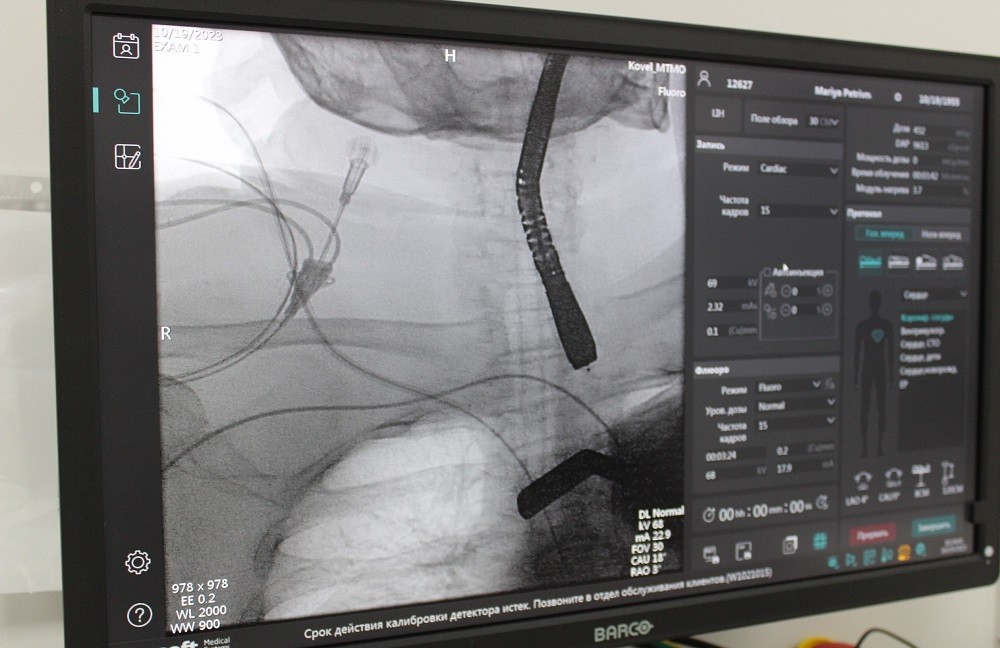

Вперше на Волині операцію TAVI (транскатетерну імплантацію аортального клапана) на серці виконали у Ковельському МТМО! Команда фахівців Центру дитячої кардіології та кардіохірургії (м. Київ) на запрошення Ковельського МТМО спільно з нашими лікарями успішно здійснили протезування клапана без зупинки серця та без розрізу грудної клітини. Про це повідомляє генеральний директор медичного об'єднання Валентин Вітер на стоірнці у соцмережі.

68-річна пацієнтка поступила до лікарні з критичним стенозом аортального клапана, який майже не відкривався. І це не єдиний діагноз хворої: вона страждає цукровим діабетом, має надлишкову вагу тіла та перенесла інсульт. Врятувати життя жінки могла лише мініінвазивна операція, адже відкрите оперативне втручання їй протипоказане.

Основний етап імплантації клапана виконав Володимир Танський, завідувач кардіохірургічного центру Ковельського МТМО. Загалом до проведення операції було залучено чимало місцевих лікарів: Анатолій Бондарчук, Сергій Прудкой, Тарас Окунь, Павло Андреєв, Ольга Танська. Разом з фахівцями Центру дитячої кардіології та кардіохірургії, вони показали злагоджену командну роботу, яка завершилася позитивним результатом.